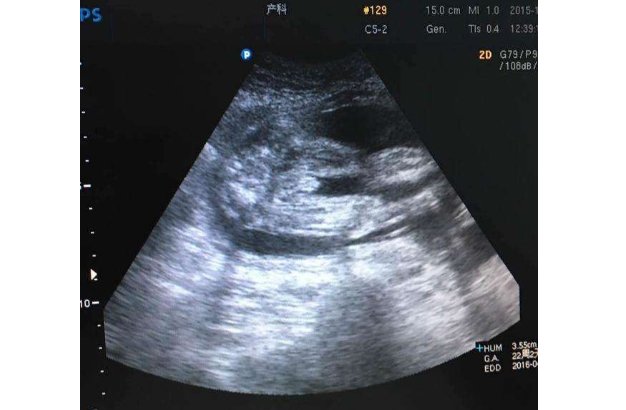

它是一种介质。介质就相当于媒婆,比如,声音在空气中传播,那么空气就是声音的一种传播介质。比如电流在水里可以传播,那么水就成了电流的传播介质。同样的,超声耦合剂,顾名思义就是超声波的传播介质,原本超声波透过身体是有阻碍的,不是很好穿透,皮肤就是我们的保护层。现在,通过涂上超声耦合剂,就可以将超声波完美的传播到身体内,从而更好的观察到身体内的影像。